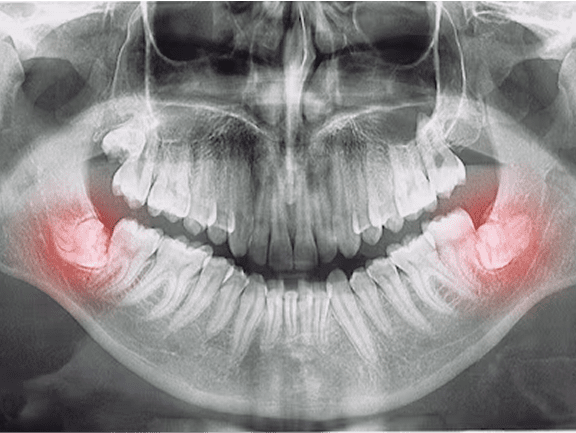

Impacted teeth

Sometimes adult teeth don’t emerge on schedule because they are blocked by other teeth in a crowded young mouth. Expansion widens the space available for adult teeth to erupt without interference.